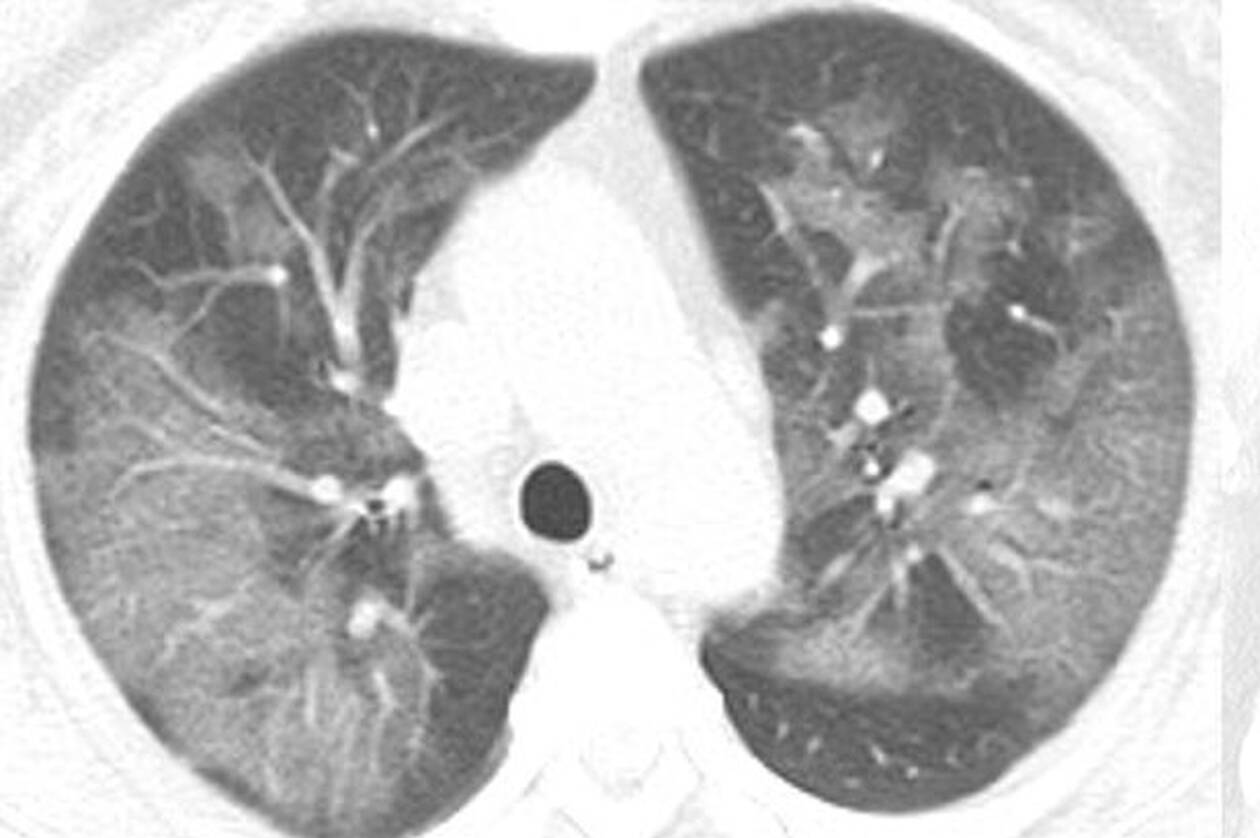

Η πανδημία του κοροναϊού covid-19 συνεχίζει να καλπάζει σε όλο τον πλανήτη, με τους γιατρούς να παρακολουθούν την έξαρσή του. Περισσότεροι από 4.000 άνθρωποι έχουν χάσει τις ζωές τους από τις επιπλοκές του ιού, ο οποίος προκαλεί σοβαρό πρόβλημα στους πνεύμονες των ασθενών. Στην δημοσιότητα δόθηκαν από την Ραδιολογική Κοινότητα της Βορείου Αμερικής ακτινογραφία πνευμόνων ασθενών, οι οποίοι είχαν προσβληθεί από τον κοροναϊό, οι οποίες προκαλούν ανατριχίλα.

Οι ασθενείς που έχουν νοσήσει μέχρι στιγμής έχουν περιγράψει την εμπειρία τους ως μια «τρομακτική προσπάθεια για να αναπνεύσουν». Στις ακτινογραφίες διακρίνονται κάποια άσπρα σημάδια, χαμηλά στους πνεύμονες. Περιγράφονται ως υγρό στις κυψέλες του πνεύμονα. Να σημειώσουμε πως οι ακτινογραφίες αυτές που δόθηκαν στην δημοσιότητα είναι από ασθενείς από την Κίνα που νόσησαν με επιπλοκές, οπότε δεν έχουν καμία σχέση με το αν νοσήσει κάποιος ο οποίος δεν αντιμετωπίζει προβλήματα υγείας.